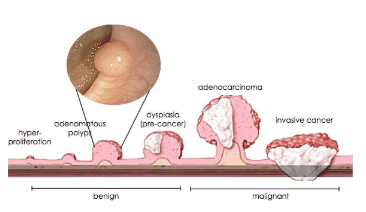

Thành đại tràng chúng ta gồm các lớp niêm mạc, lớp dưới niêm mạc, lớp cơ và lớp thanh mạc. Theo các nghiên cứu, việc loại bỏ tổn thương khi tổn thương chưa xâm lấn lớp niêm mạc sẽ có tiên lượng rất tốt.

Trên thực tế, có những polyp rất nhỏ, chừng 5mm (thông thường polyp 5mm ít có khả năng hoá ác), nhưng đã có ung thư hoá bề mặt, và điều này chỉ được phát hiện sau khi đã có kết quả giải phẫu bệnh sau cắt trọn polyp. Đối với nhưng trường hợp như vậy, bệnh nhân phải làm thêm một số xét nghiệm như CT Scan bụng chậu, CEA, CA 19.9…để đánh giá giai đoạn tổn thương, và đôi khi phải tiến hành phẫu thuật cắt bỏ đoạn ruột chứa tổn thương ung thư, nếu polyp xâm lấn.

Đặc điểm của một số polyp nghi ung thư hóa: bề mặt có khuynh hướng lan rộng, bề mặt polyp có loét hoặc viêm trợt, các nếp niêm mạc ruột hội tụ về phía polyp, polyp dạng “đặc”, polyp dạng lõm với phần trung tâm nhô lên.

Đối với những dạng hình ảnh như vậy, bác sĩ nội soi cần cân nhắc trước khi cắt polyp, vì có thể mức độ ung thư xâm lấn của polyp đã đến lớp dưới niêm, và việc cắt polyp qua nội soi không đảm bảo an toàn mặt ung thư.

Đối với các polyp có vi bề mặt (quan sát trên nội soi phóng đại ) không đều, các vi mạch máu bề mặt dãn, xoắn, đứt đoạn, đường kính không đều… sẽ được phân loại vào dạng các polyp có nguy cơ xâm lấn xuống lớp dưới niêm, và việc cắt polyp qua nội soi sẽ không đảm bảo về phương diện ung thư.

Polyp ung thư hoá thường có khuynh hướng xâm lấn xuống các lớp phía dưới. Đầu dò siêu âm được đưa đến tổn thương, việc đánh giá mức độ xâm lấn đến lớp dưới niêm, lớp cơ của thành ống tiêu hoá, giúp tiên lượng khả năng cắt polyp được qua nội soi hay không.